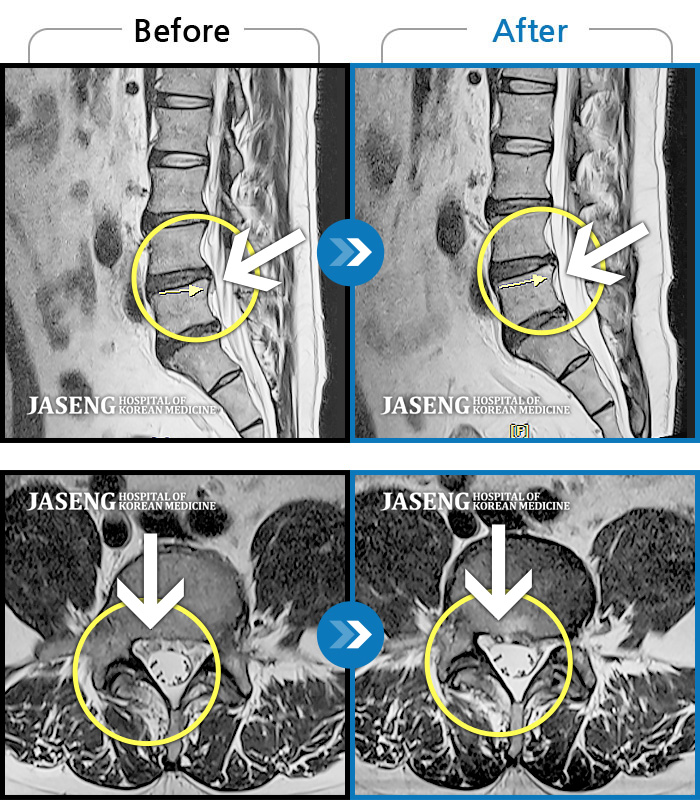

허리디스크

광주 · 김동은 원장

양측 허리부터 양측 골반까지 당기는 통증, 양측 하지 후면으로 이어지는 통증

촬영시기

2022.09.05 ~ 2024.05.06

2024.05.24